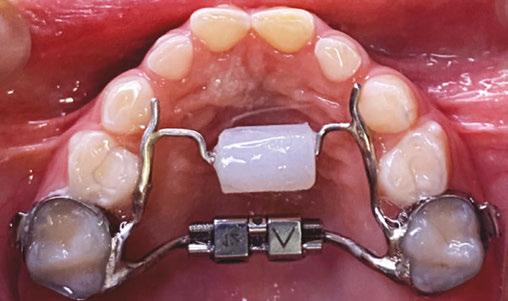

The history of myofunctional therapy in conjunction with orthodontic treatment dates to as early as 1906 with the publication of American orthodontist Alfred Rodgers’ “Living Orthodontic Appliance.” Rodgers presumed that muscle alone would correct a malocclusion.1 To further this claim, Edward Angle theorized that “every malocclusion has a myofunctional cause.”2 Angle’s contribution to myofunctional therapy relied primarily on fixed orthodontic appliances (Figure 1). However, the myofunctional component of orthodontics with fixed appliances fell out of favor when relapse occurred in a high percentage of patients coupled with time-consuming techniques to achieve results. Hence, tooth-centered orthodontics with extractions or self-ligating brackets without the need for extractions grew in popularity (Figure 2). Nevertheless, post-orthodontic relapse was still problematic, requiring permanent retainers. As George Hahn once wrote in his publication “Retention — The Stepchild of Orthodontia,” Irrespective of the length of time a tooth is held in its new position … upon release, it will seek a place where it is in balance.”3 Myofunctional therapy has made significant strides in using specifically designed exercises to bring oral, facial, and